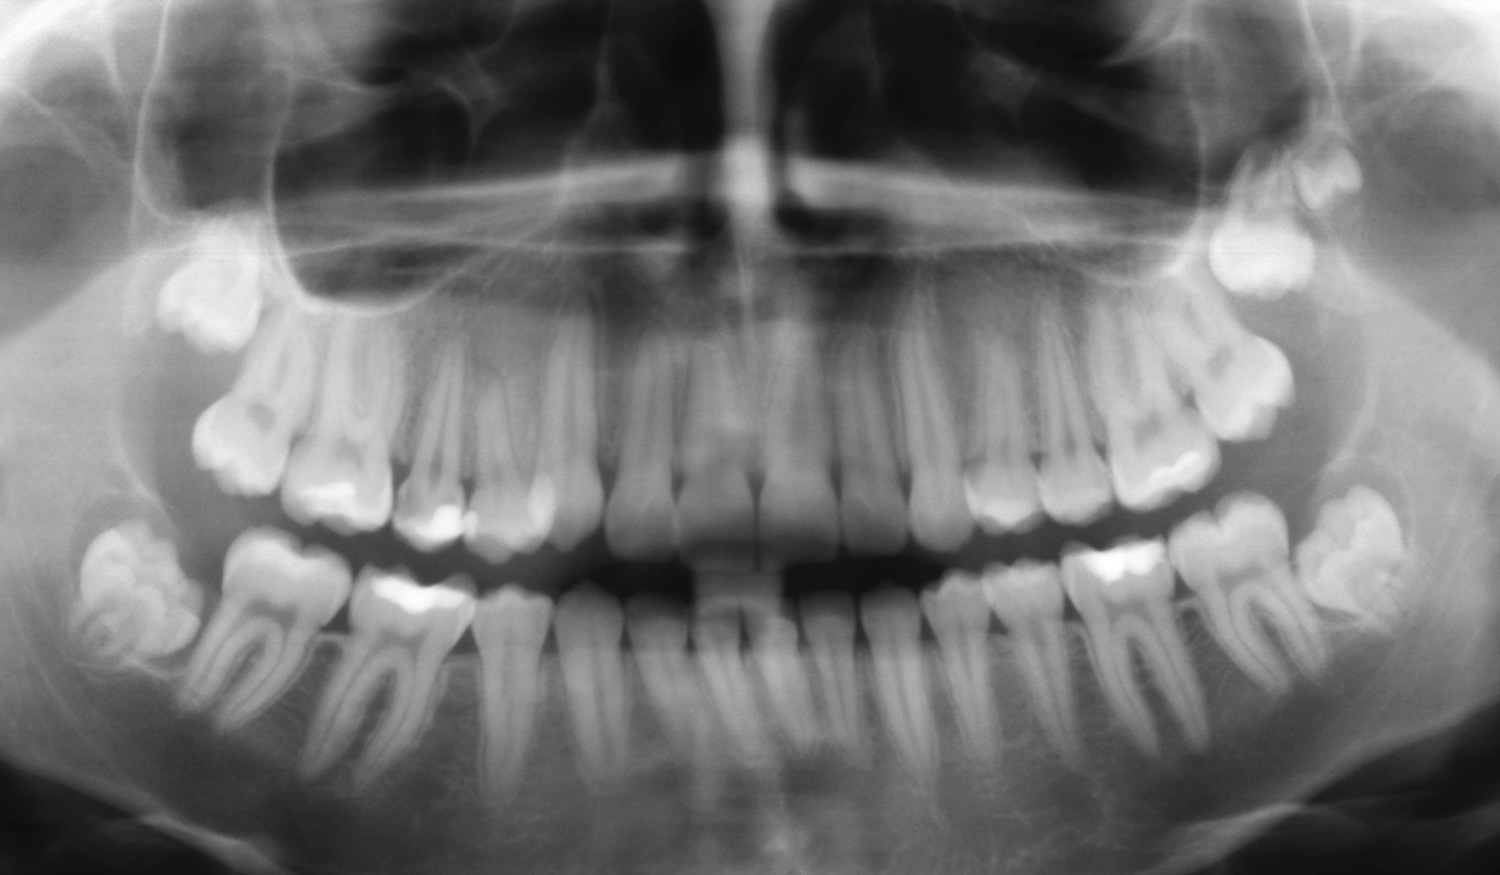

• Problemas na erupção, ou seja, mau posicionamento do dente na arcada dentária. Esta descoberta consegue-se pelas radiografias, daí a importância das visitas ao dentista.